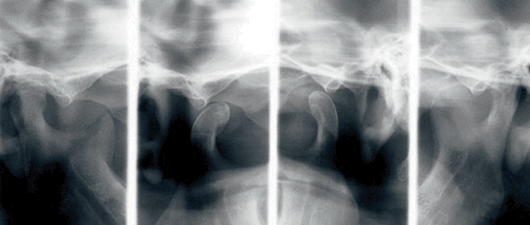

Oprogramowanie CS 8100 wyposażono

w najnowsze algorytmy przetwarzania obrazu.

Dzięki nim zminimalizowano cień kręgosłupa na

pantomogramach. Aparat generuje jasne i ostre

obrazy cyfrowe